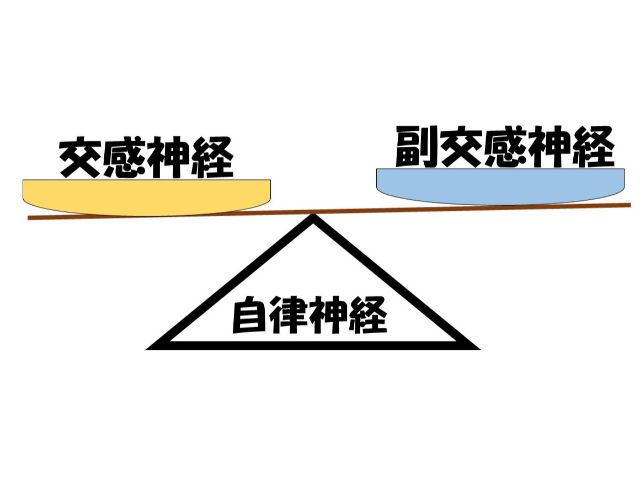

2. 交感神経と副交感神経

【自律神経を少し詳しくみていくと・・】

自律神経は2つに分けられます。

- 交感神経

- 副交感神経

交感神経は・・

●朝起きてから少しずつ高まります

●体を動かすための神経

●または活動するための神経です

副交感神経は・・・

●リラックスする時に働きます

●体の修復をするための神経

●内臓を働かせる役割もあります

ポイントはこの交感神経と副交感神経を

しっかりと働かせること!

自律神経というと

「バランスが大切」という考え方もあります。

しかし当院は

- バランス

- 交感神経と副交感神経がしっかりと働くこと

以上の2つが大切だと考えています。

例えば交感神経神経と副交感神経が最大で「10」働くとします。

しかし交感神経と副交感神経の両方が「3」しか働かない。

これは両方「3」なのでバランスは取れています。

しかし残りの「7」働いていません。

これではいくらバランスがとれていても自律神経が「10」の力で働けないのです。

副交感神経が「3」なのでしっかりと体を回復させる事ができません。

そのため「だるさ」を感じやすくなることもあるでしょう。

また交感神経も「3」なので

自分の思い通りに身体を動かすことが難しくなるでしょう。

そのためやる気が起きない状態になります。

このように自律神経は

「バランス」と「しっかりと働く事」が重要なのです。